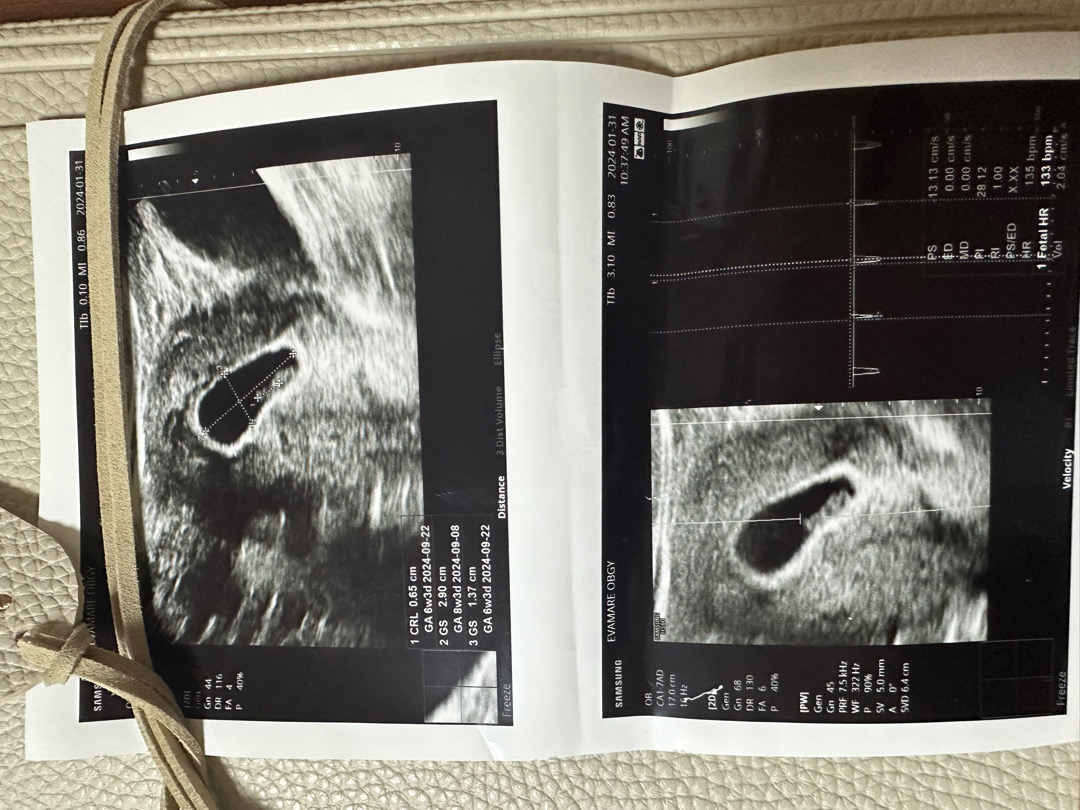

6주4일 배초음파

보고싶어서 오늘도 세복이보러 다녀왔어요◡̈ 이때쯤 배초음파로하면 잘 안보인다하셨는데 너무 잘보이고 두번째로 듣는 심손데 133bpm으로 잘 뛰어주네요◡̈ 울 아가 넘 고맙다 사랑해🐉💚